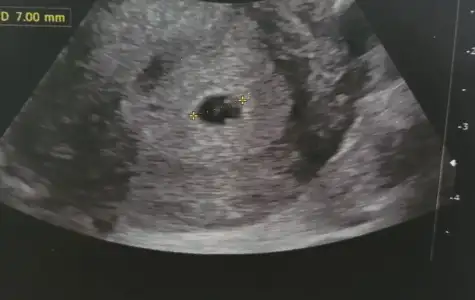

Merhaba kızlar biz bu sabah keseyi gördük.10mm ve 7 haftalık.çok şükür bir aşamayı daha atlattık.

Benim 5+3 kese 7mm

Benimde siyah beyaz olan 5. Haftamın ultrasonu. Renkli olan dün acilde doktorun çektiği ultrason yani 7. Hafta. Kesede büyüme var ama yolk saçını görmedi. Çok huzursuz oldum.